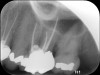

Fig 4. Preoperative radiograph showing aggressive external root resorption and thin dentinal walls.

Figure 4

Clinical procedure: Regeneration of the endodontic pulp space is indicated for cases with very thin dentinal walls and an open apex that is more than 1 mm in diameter radiographically (Figure 4). Disinfection of the root canal system is performed using sodium hypochlorite irrigation followed by a triple antibiotic paste dressing that is left in place for 1 week. At the second visit, ethylenediaminetetraacetic acid (EDTA) is used to condition the dentin walls, which results in the release of growth factors, and bleeding is stimulated in the periapical tissues (where stem cells are located), with the aim of filling the pulp space with a stable blood clot, which would serve as the scaffold. MTA is then placed at the canal orifice in contact with the clot to protect it from coronal microleakage (Figure 5 and Figure 6). In time, the clot should be replaced with a reparative tissue of variable composition, and the root walls should continue to thicken due to the deposition of a dentin-like material on the pre-existing root dentin27,28 (Figure 7 and Figure 8).